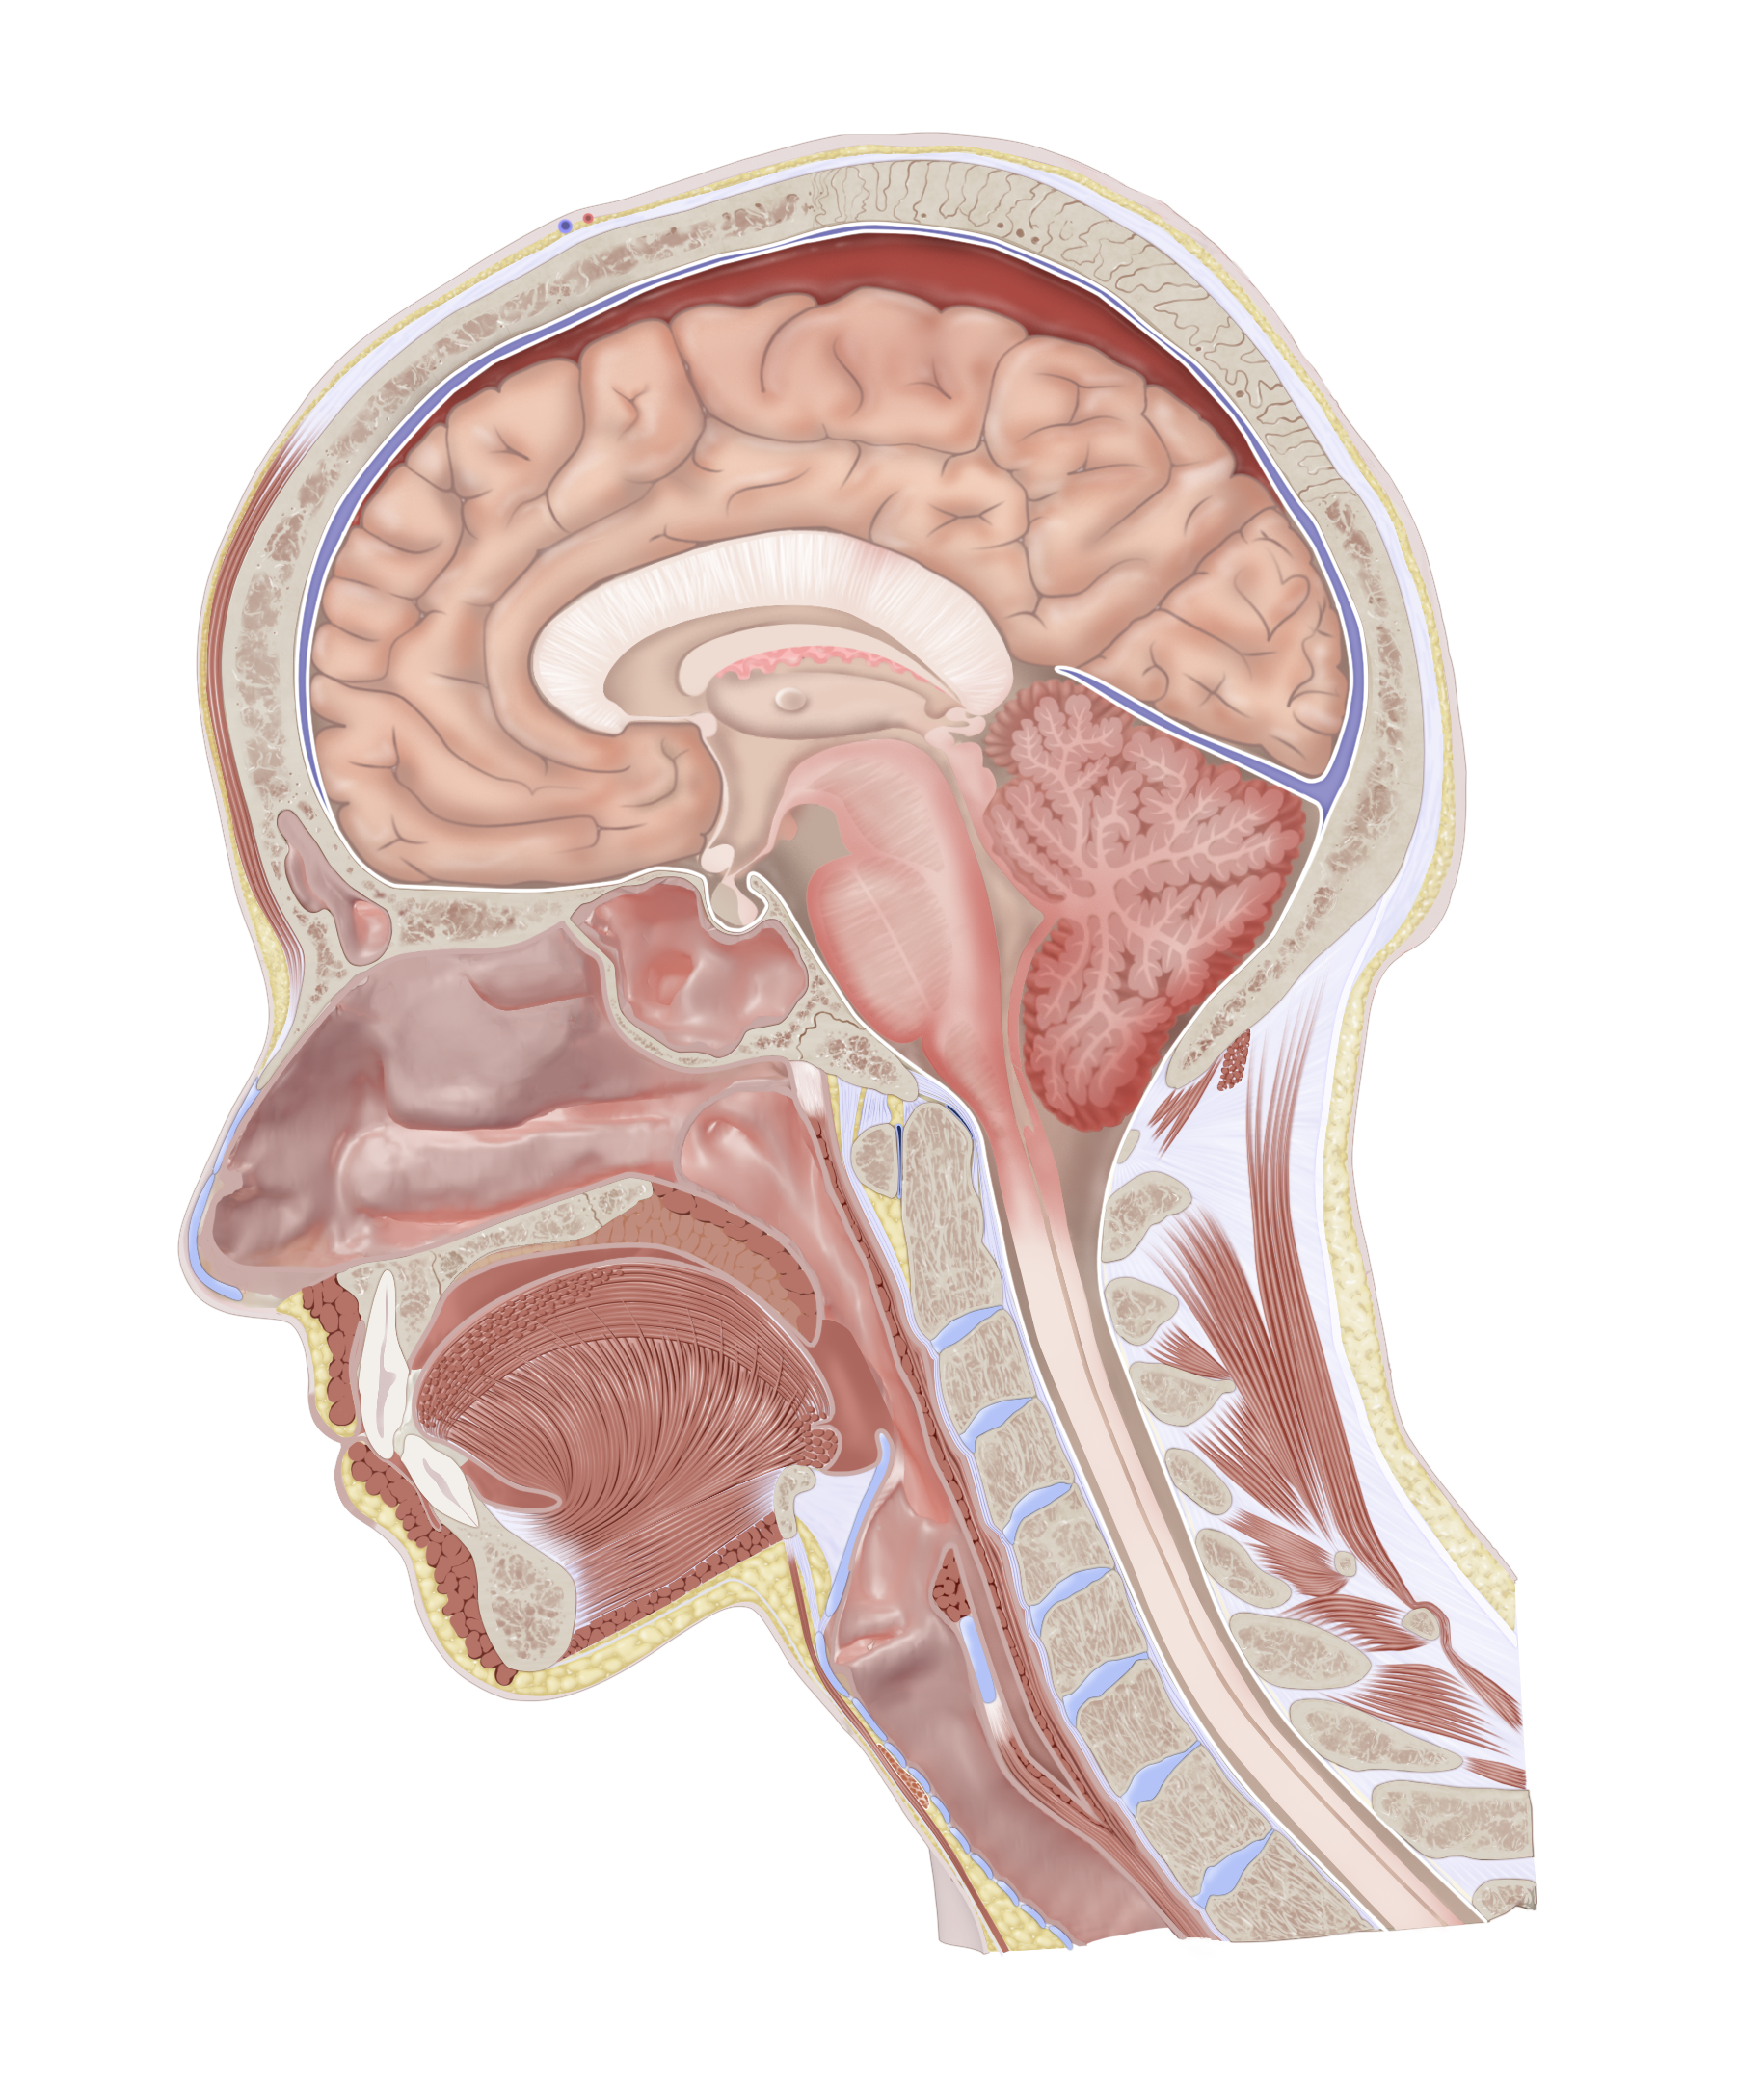

Subdural Hematoma in Head Cross Section

Demonstration of a subdural hematoma resulting in increased intracranial pressure, brainstem compression, and tonsillar herniation of the cerebellum.